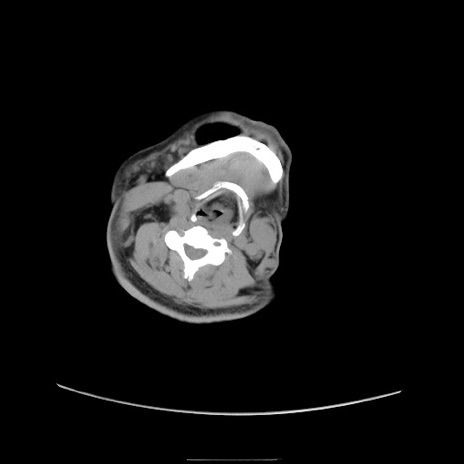

症例22(横断像)

【症例】50歳代男性

【主訴】腹痛

【現病歴】AVMからの被殻出血のため回復期リハ病棟入院中。 本日午後3時頃急に下腹部痛が出現した。

【既往歴】AVM、被殻出血、虫垂炎、高血圧

【身体所見】意識晴明、左半身不全麻痺、会話の理解は良好、36.5°C、腹部:膨隆、全体に板状硬、下腹部正中に圧痛点あり、反跳痛-、筋性防御不明、右下腹部にope scar

【データ】WBC 9400、CRP 0.06